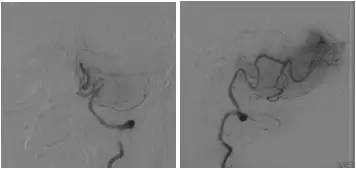

DSA:右侧椎动脉V4段重度狭窄,前向血流减慢,基底动脉近中段未见顺行显影,左侧椎动脉V4段远心端闭塞,右后交通动脉开放,经右颈内动脉造影可见基底动脉中远段显影,左胚胎型大脑后动脉(图3-5)。

图3

图4

图5